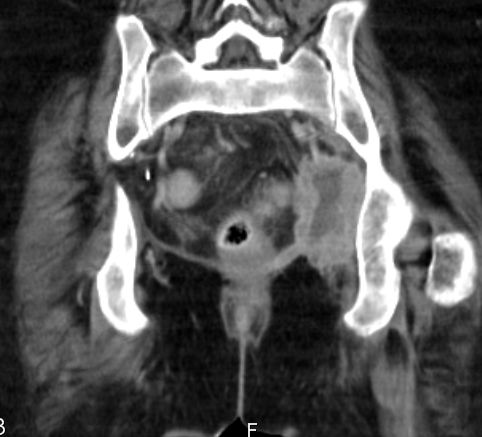

| Becken-Rezidiv | 54-jährige Frau nach radikaler Zystektomie und Anlage eines Ileumconduits wegen eines Plattenepithelkarzinoms der Harnblase vor 8 Monaten. Jetzt Verdacht eines Abszesses an der linken Beckenwand. Anlage eines Transversostomas und Drainage, später transvaginale Drainageeinlage. Jetzt Tumorfreilegung, Nekroseausräumung, Drainage. Histologie: Plattenepithelkarzinom. Destruktion des Beckenknochens links mit Einbruch ins Acetabulums. | ||